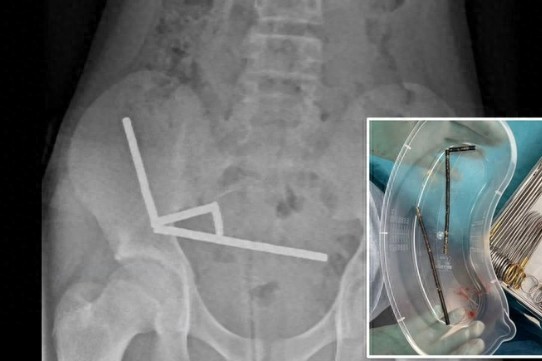

近日,新西兰一名13岁男孩因腹痛住院,经检查后承认他在一周前吞下大约100颗小型强力磁铁,这些磁铁约5毫米×2毫米,从线上平台购得。医生在男孩多处肠道发现四条长链排列的磁铁束,最终不得不切除部分肠道以挽救生命。  一名来自新西兰的13岁男孩因腹痛四天入院检查,最终承认他在一周前吞下大约80至100颗小型高力量稀土磁铁。放射线检查发现,这些磁铁在其肠道内分别沿四条长线排列,形成罕见的异物吞食案例。 该男孩从线上商店购买这些尺寸为5 毫米×2 毫米的磁铁,因胃肠道异常吸引,医师判定需进行重大手术取出。虽然仅8日后即可出院,但他因此失去部分肠道。 奥克兰大学教授亚历克斯·辛姆斯指出:“此案证明,吞食这类小型高力量磁铁极具生命危险性。这些磁铁往往作为成人或儿童玩具销售,外观醒目易吸引儿童吞食。” 事实上,多年来儿童吞食磁铁的案例屡见不鲜。2024年,美国一名8岁男孩因吞食磁铁集群导致肠堵塞死亡。今年早些时候,一位7岁男孩亦因吞食桌游内磁铁而送急诊。 根据研究显示,虽然单颗磁铁通常能自行排出,但若多颗同时吞入,这些高力量磁铁可能在胃肠壁两侧互相吸引,压迫组织造成灼伤、穿孔、阻塞等重症。 潇湘晨报综合报道